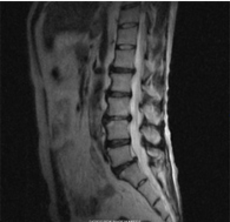

●腰椎椎間板ヘルニアと腰椎分離すべり症の手術を回避できました。

C・Nさん 49歳 男性

一年半前に自宅で重いものを持ち上げた際に、腰に激痛が走り、左足の痛みとシビレで歩けなくなりました。

整形外科では「腰椎椎間板ヘルニア」、「腰椎分離すべり症」と診断され、痛み止めと運動療法で痛みが治まっていました。

しかし、それから半年経ってまた、腰痛と左足の痛みとシビレが出てきて、神経根ブロック注射の後、2ヶ月くらい掛かって痛みが和らいでいきました。

ところがそれから更に1年経った今年になって、また同じ症状が現れ、整形外科を受診すると、腰椎椎間板ヘルニアが3か所あり、神経根ブロック注射をうけましたが、今回は効果がありませんでした。

「腰椎椎間板ヘルニア」と「腰椎分離すべり症」の手術を前提で通院治療している折に知人からなるほ堂仙骨調整を紹介され、「手術せず治ってくれれば」と、神頼みにも似た心境で施術を受け始めました。

腰椎椎間板ヘルニアと腰椎分離すべり症の手術を回避できましたなるほ堂仙骨調整を受ける前は、腰が痛くて寝床から起き上がるのがやっとで、歩くこともできませんでした。家から車でなるほ堂まで通う25分の間にも腰が痛くなってきていました。

週2回のサイクルで仙骨調整を受け始め、腰痛は楽になったりまた更に痛くなったりしながら10回目までは、それほど大きな変化は感じていませんでした。ちょうどその時期に、手術のための検査入院で、いままでブロック注射をしていない神経根部に注射をしましたが効果ないばかりか、余計に腰と足の痛みが増しました。更に、検査のため脊髄に造影剤を注射した後、頭が痛くなってしばらく動けない状態が続きました。そのような状態でも、医者はあまり気にしてくれなかったことや、ヘルニアの手術だけでは治らない可能性があるから、腰椎分離すべり症の手術で仙骨と腰椎をボルトで止めてしまうという手術内容や術後2から3カ月経たないと仕事に復帰できないという説明を聞いて、手術を受けることへの迷いが出てきました。

腰椎椎間板ヘルニアと腰椎分離すべり症の手術を回避できましたそうして、11回目の施術後から、腰と足の痛みが軽減してきました。なるほ堂仙骨調整で腰痛が軽減されていく可能性を感じ、気負いが無くなってきました。

それから1カ月経った今もよい状態が続いています。手術は中止しました。手術が成功しても10月頃と思っていた会社復帰の夢も施術を受け始めてから2カ月半で叶いました。

初回のときに「まずは、3カ月続けてみましょう。」という先生の説明が思い出されます。

ほとんど歩けなかったのが、今では30分は、足に違和感なしに歩けるまでに回復しています。さらなる改善を目指して、会社に通いながらも、週1回のなるほ堂仙骨調整を続けていこうと思っています。